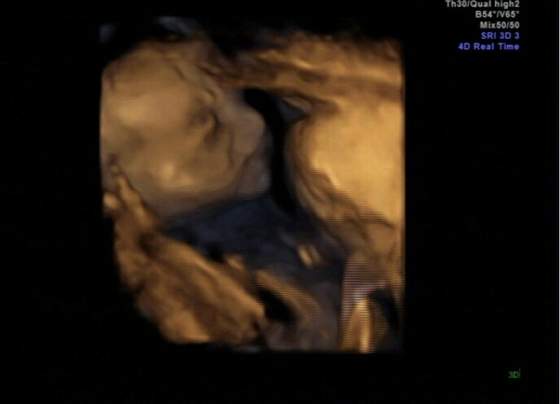

Kropek ale śliczne fotki! Takie super wyraźne. Cudna pamiątka :-)

kropekk na kopie juz widze

super i jak buzke otworzyl/a ja nie moge ale to fajne tez chce juz